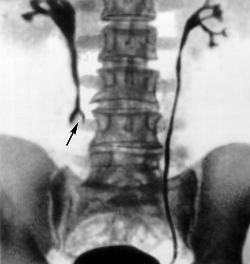

Стриктура мочеточника

стриктура правого мочеточника - рентгенограммаСтриктура мочеточника - сужение его просвета. Она может располагаться в различных отделах мочеточника и иметь различную протяженность. По происхождению патология может носить врожденный и приобретенный характер. Наиболее частой локализацией врожденной стриктуры является место перехода лоханки в мочеточник, и переход мочеточника в мочевой пузырь. К врожденным сужениям относят также сужение вызванное сдавлением мочеточника аномальным сосудом.

Диагностика основана на данных ультразвукового исследования, рентгенологических методов с применением контрастирования, а также результатах компьютерной томографии.